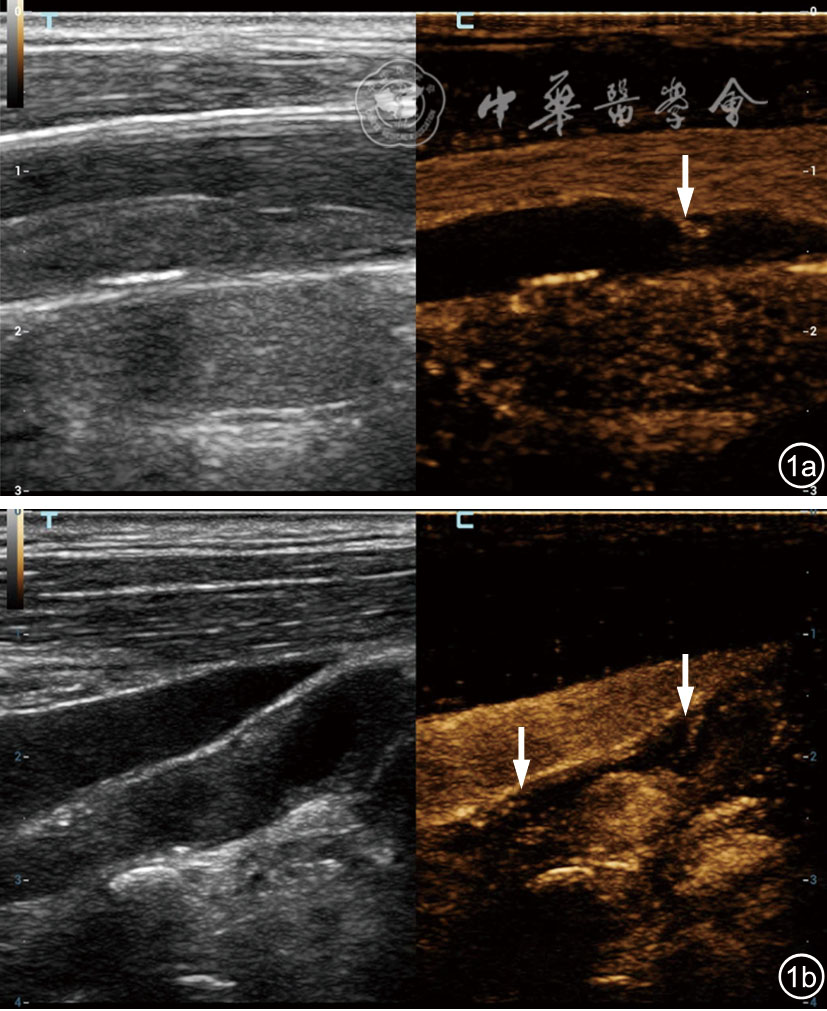

图1 颈动脉斑块内造影剂不同扩散方向的超声造影(CEUS)表现。图a为斑块纤维帽破裂的典型超声表现(左图为常规超声,右图为CEUS),可见造影剂从血管腔内进入斑块,呈“内向外”扩散(白色箭头);图b为斑块内新生血管形成的典型超声表现(左图为常规超声,右图为CEUS),可见造影剂从血管外膜流入斑块,呈“非内向外”扩散(白色箭头)